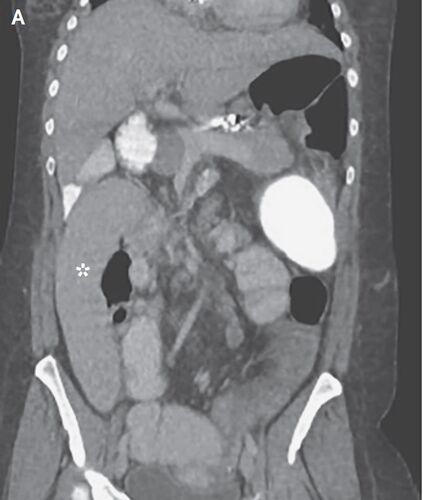

症例29:腹痛と嘔吐で受診した36歳女性(N Engl J Med. 2020 Nov 19;383(21):2065.)

病歴/身体所見 ・36歳女性 ・前日からの腹痛と嘔吐のためER受診 ・潰瘍性大腸炎、原発性硬化性胆管炎による肝硬変を患っている ・手術歴:結腸全摘術、胆嚢摘出術、虫垂切除術 ・触診では腹部全体に圧痛を認めた 検査 ・血液検査:lipase 682IU/L(5~50)と上…